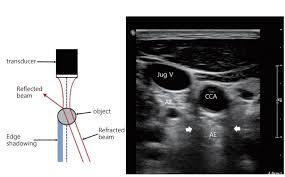

경동맥 초음파 검사란, 초음파 장비를 사용하여 목 부위의 경동맥 상태를 실시간으로 검사하는 방법입니다. 이 검사는 주로 경동맥의 혈류 속도, 혈관의 두께, 그리고 플라크의 존재 여부를 평가하여, 경동맥 초음파 검사로 알 수 있는 병을 진단합니다. 검사 과정은 매우 간단하며, 환자는 편안한 자세로 누운 상태에서 초음파 탐촉자를 목 부위에 대고 진행됩니다. 일반적으로 검사 시간은 10~15분 정도 소요되며, 검사 후 당일에 결과를 확인할 수 있어 빠른 조치가 가능합니다.

경동맥 죽상경화증은 경동맥의 벽에 콜레스테롤이나 칼슘이 침착되어 두꺼워지는 병입니다. 경동맥 초음파 검사로 알 수 있

는 병 중 가장 흔한 질환으로, 경동맥의 내중막 두께(IMT)를 측정하여 동맥경화증의 진행 여부를 판단할 수 있습니다. IMT가 1mm 이상이면 동맥경화가 진행되고 있다는 것을 의미합니다. 이 질환은 뇌졸중의 위험 요소로 작용하므로 조기 진단이 중요합니다.